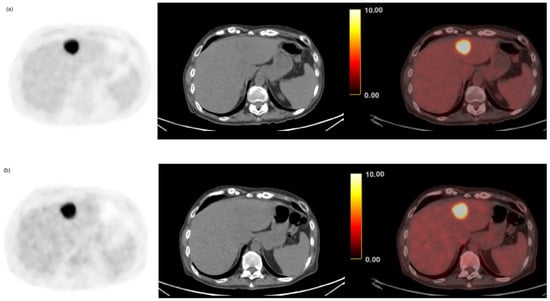

3.2. Per-Patient Performance of Early and Delayed Imaging

3.3. Semi-Quantitative and Per-Lesion Analysis

| Early | 50 | 61 | 6 | 7 | 87.7% | 91.0% | 0.04 | 88.1% |

| Delayed | 57 | 63 | 4 | 0 | 100.0% | 94.0% | 96.2% |

| CRLM | SUVmean | 5.3 ± 2.2 | 5.5 ± 3.0 | <0.001 |

| (n = 168) | SUVmax | 8.6 ± 5.4 | 9.7 ± 7.1 | <0.001 |

| TNR | 3.5 ± 2.5 | 5.4 ± 3.8 | <0.001 | |